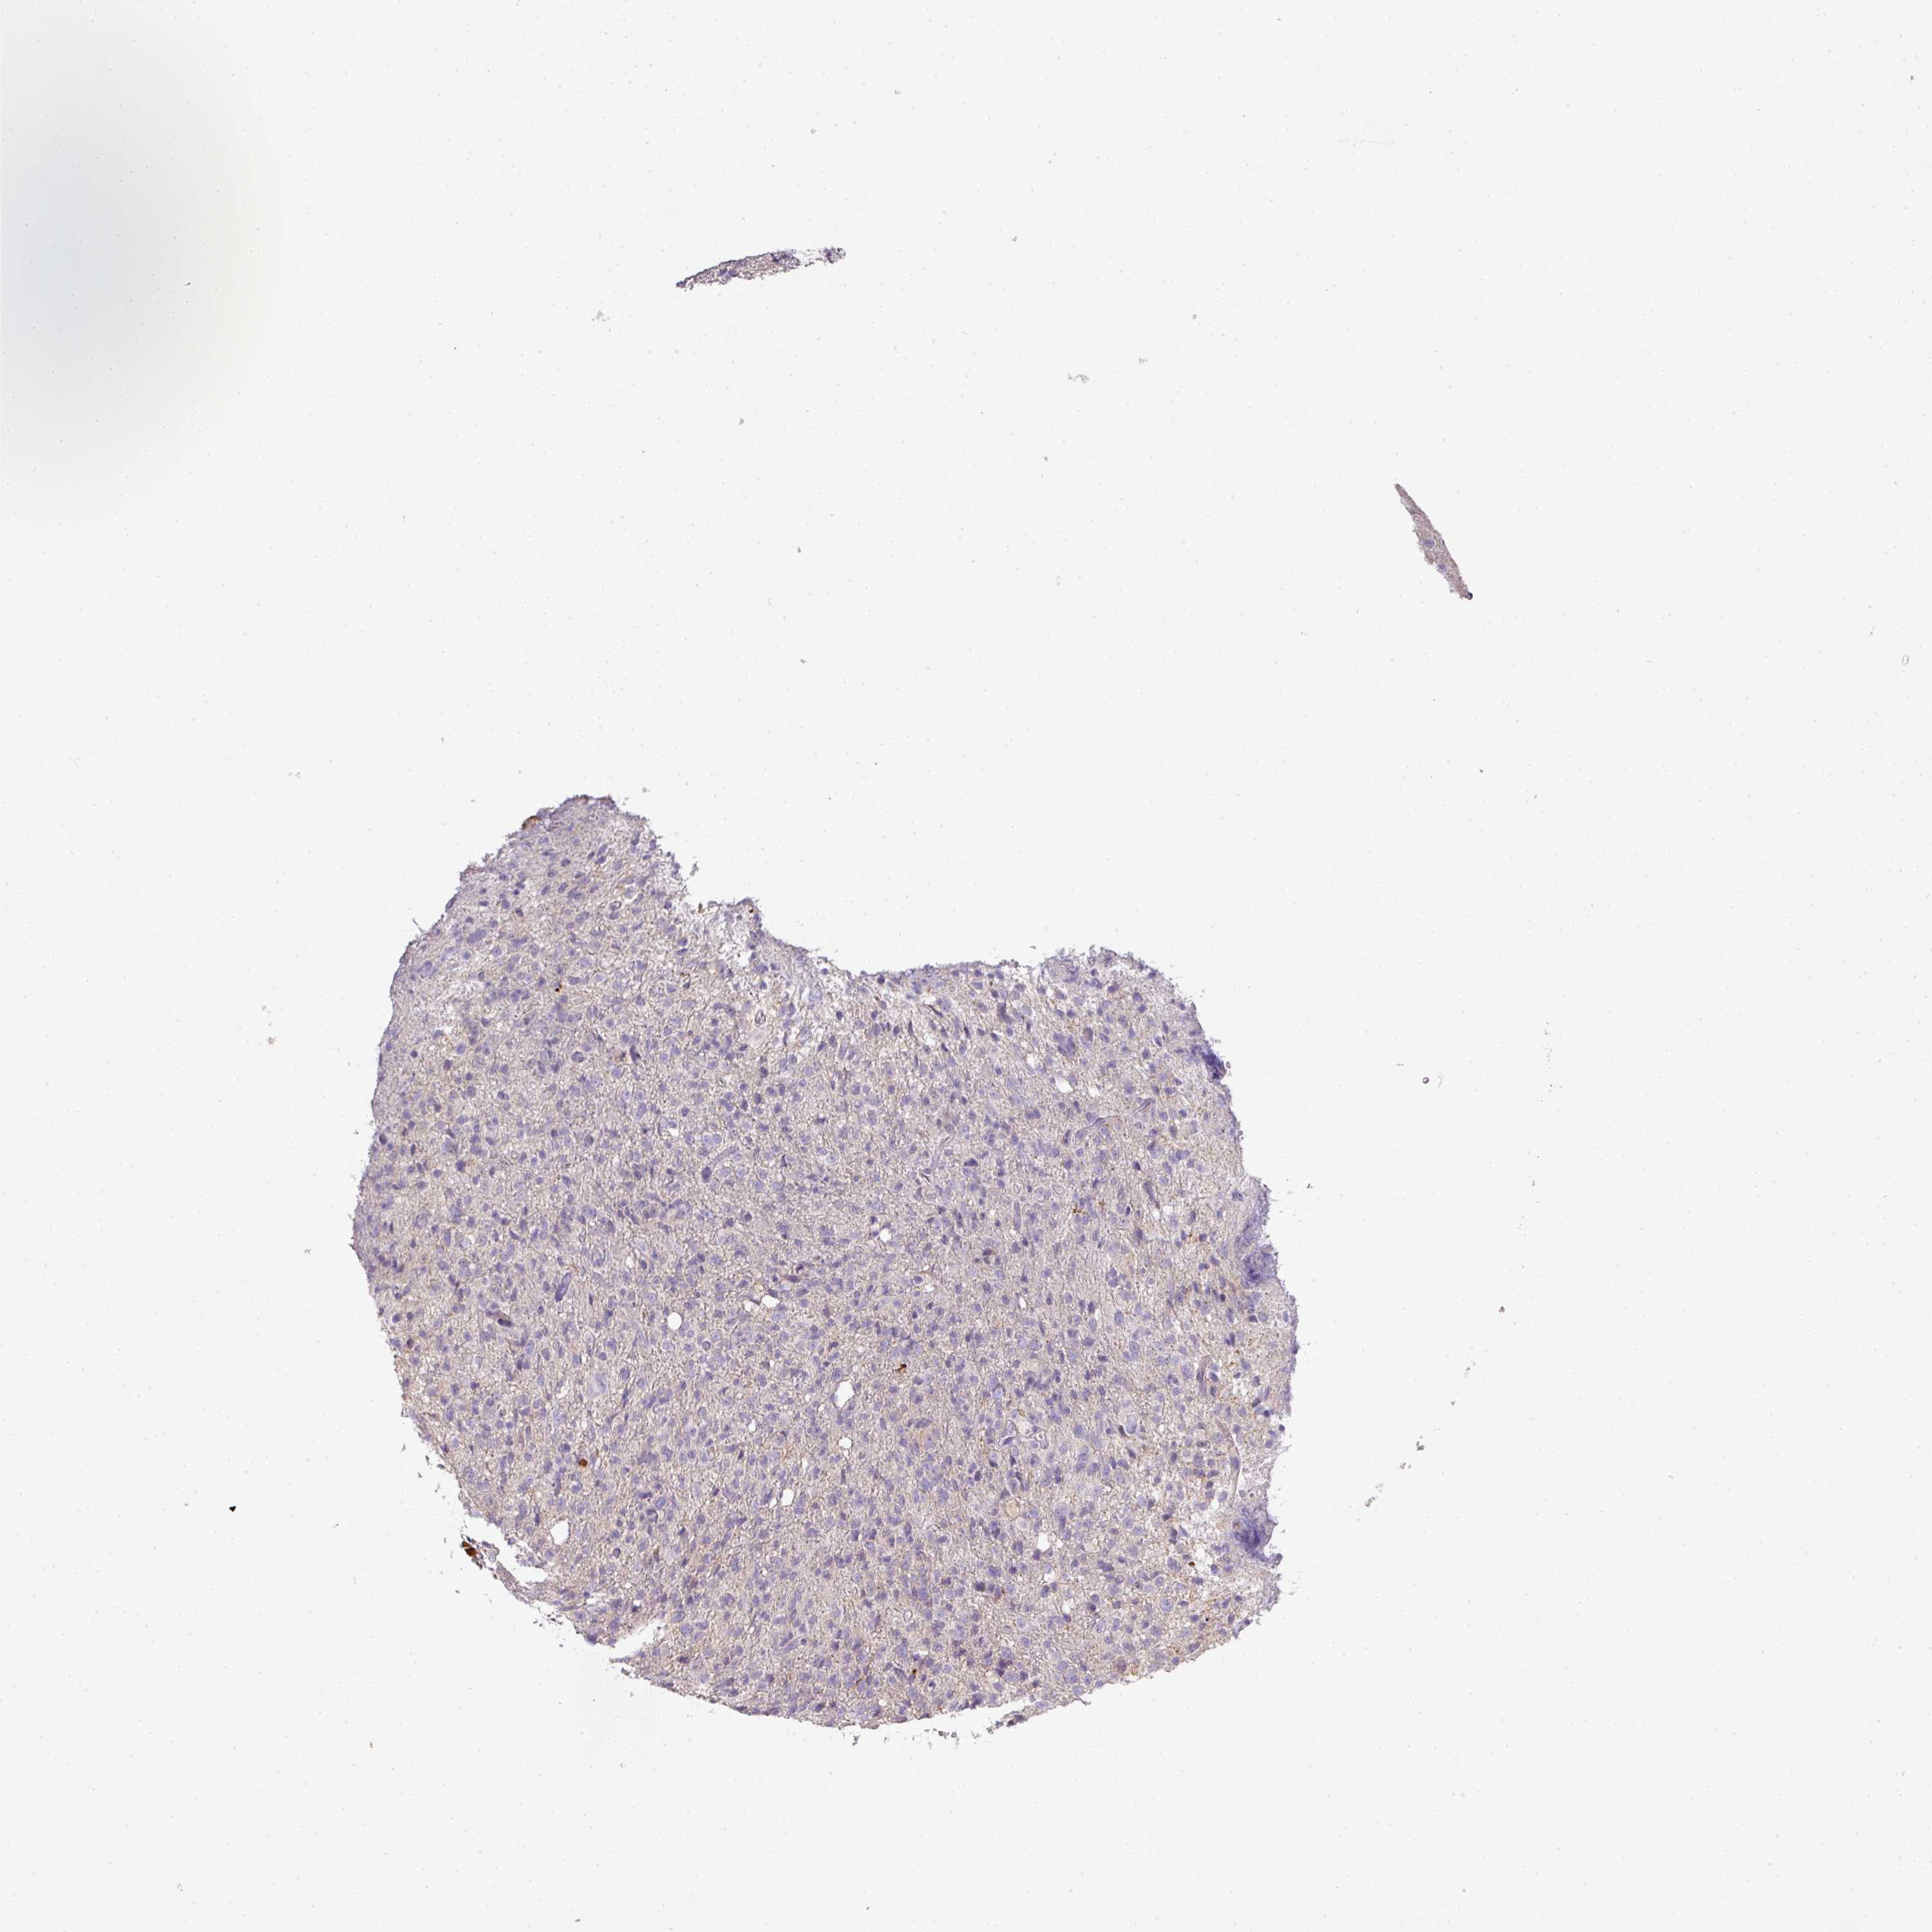

GLIOMA - Protein expressioni

A mouse-over function shows sample information and annotation data. Click on an image to view it in a full screen mode. Samples can be filtered based on level of antibody staining by selecting one or several of the following categories: high, medium, low and not detected. The assay and annotation is described here.

Note that samples used for immunohistochemistry by the Human Protein Atlas do not correspond to samples in the TCGA dataset.

Antibody stainingi

Antibody staining in the annotated cell types in the current human tissue is reported as not detected, low, medium, or high, based on conventional immunohistochemistry profiling in selected tissues. This score is based on the combination of the staining intensity and fraction of stained cells.

Each image is clickable and will lead to virtual microscopy that enables deeper exploration of all samples and also displays staining intensity scores, fraction scores and subcellular localization as well as patient and tissue information for each sample.

Antibody HPA051894

Staining

High

Medium

Low

Not detected

Intensity

Strong

Moderate

Weak

Negative

Quantity

>75%

75%-25%

<25%

None

Location

Nuclear

Cytoplasmic/membranous

Cytoplasmic/membranous,nuclear

Glioma, malignant, High grade

Glioma, malignant, Low grade

Glioblastoma, NOS